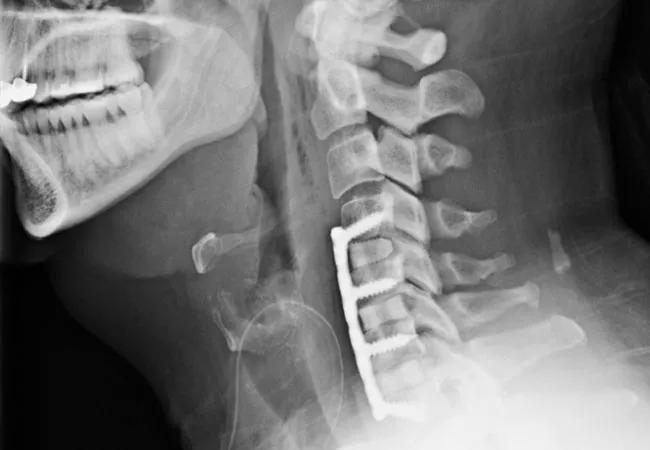

Neck X ray